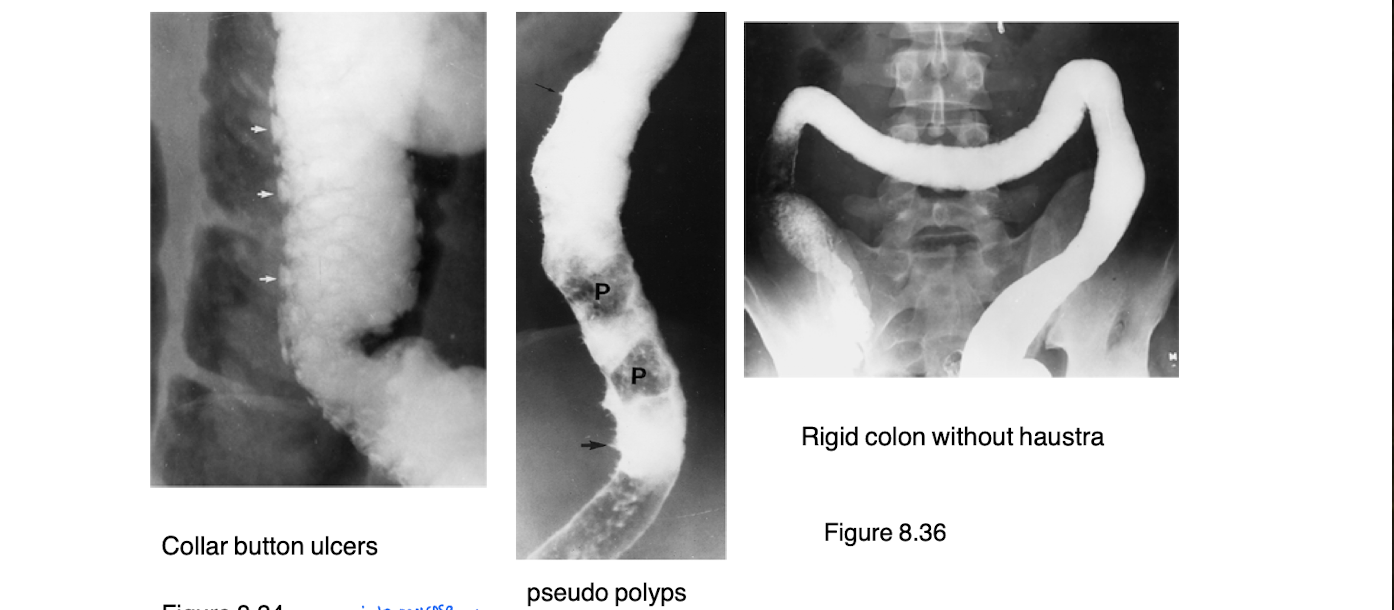

What is ulcerative colitis?

type of inflammatory bowel disease (progressive inflammatory movement)

bowel wall edema

shallow, coalescent ulcerations: pseudopolyps

prone to undergo malignant change

What is this diagnosis?

Ulcerative colitis

What are a hallmark to ulcerative colitis

No haustra

Collar button ulcers